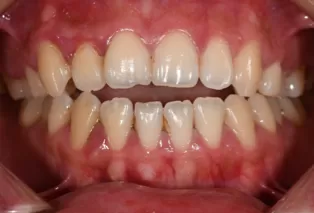

Intraoral photos